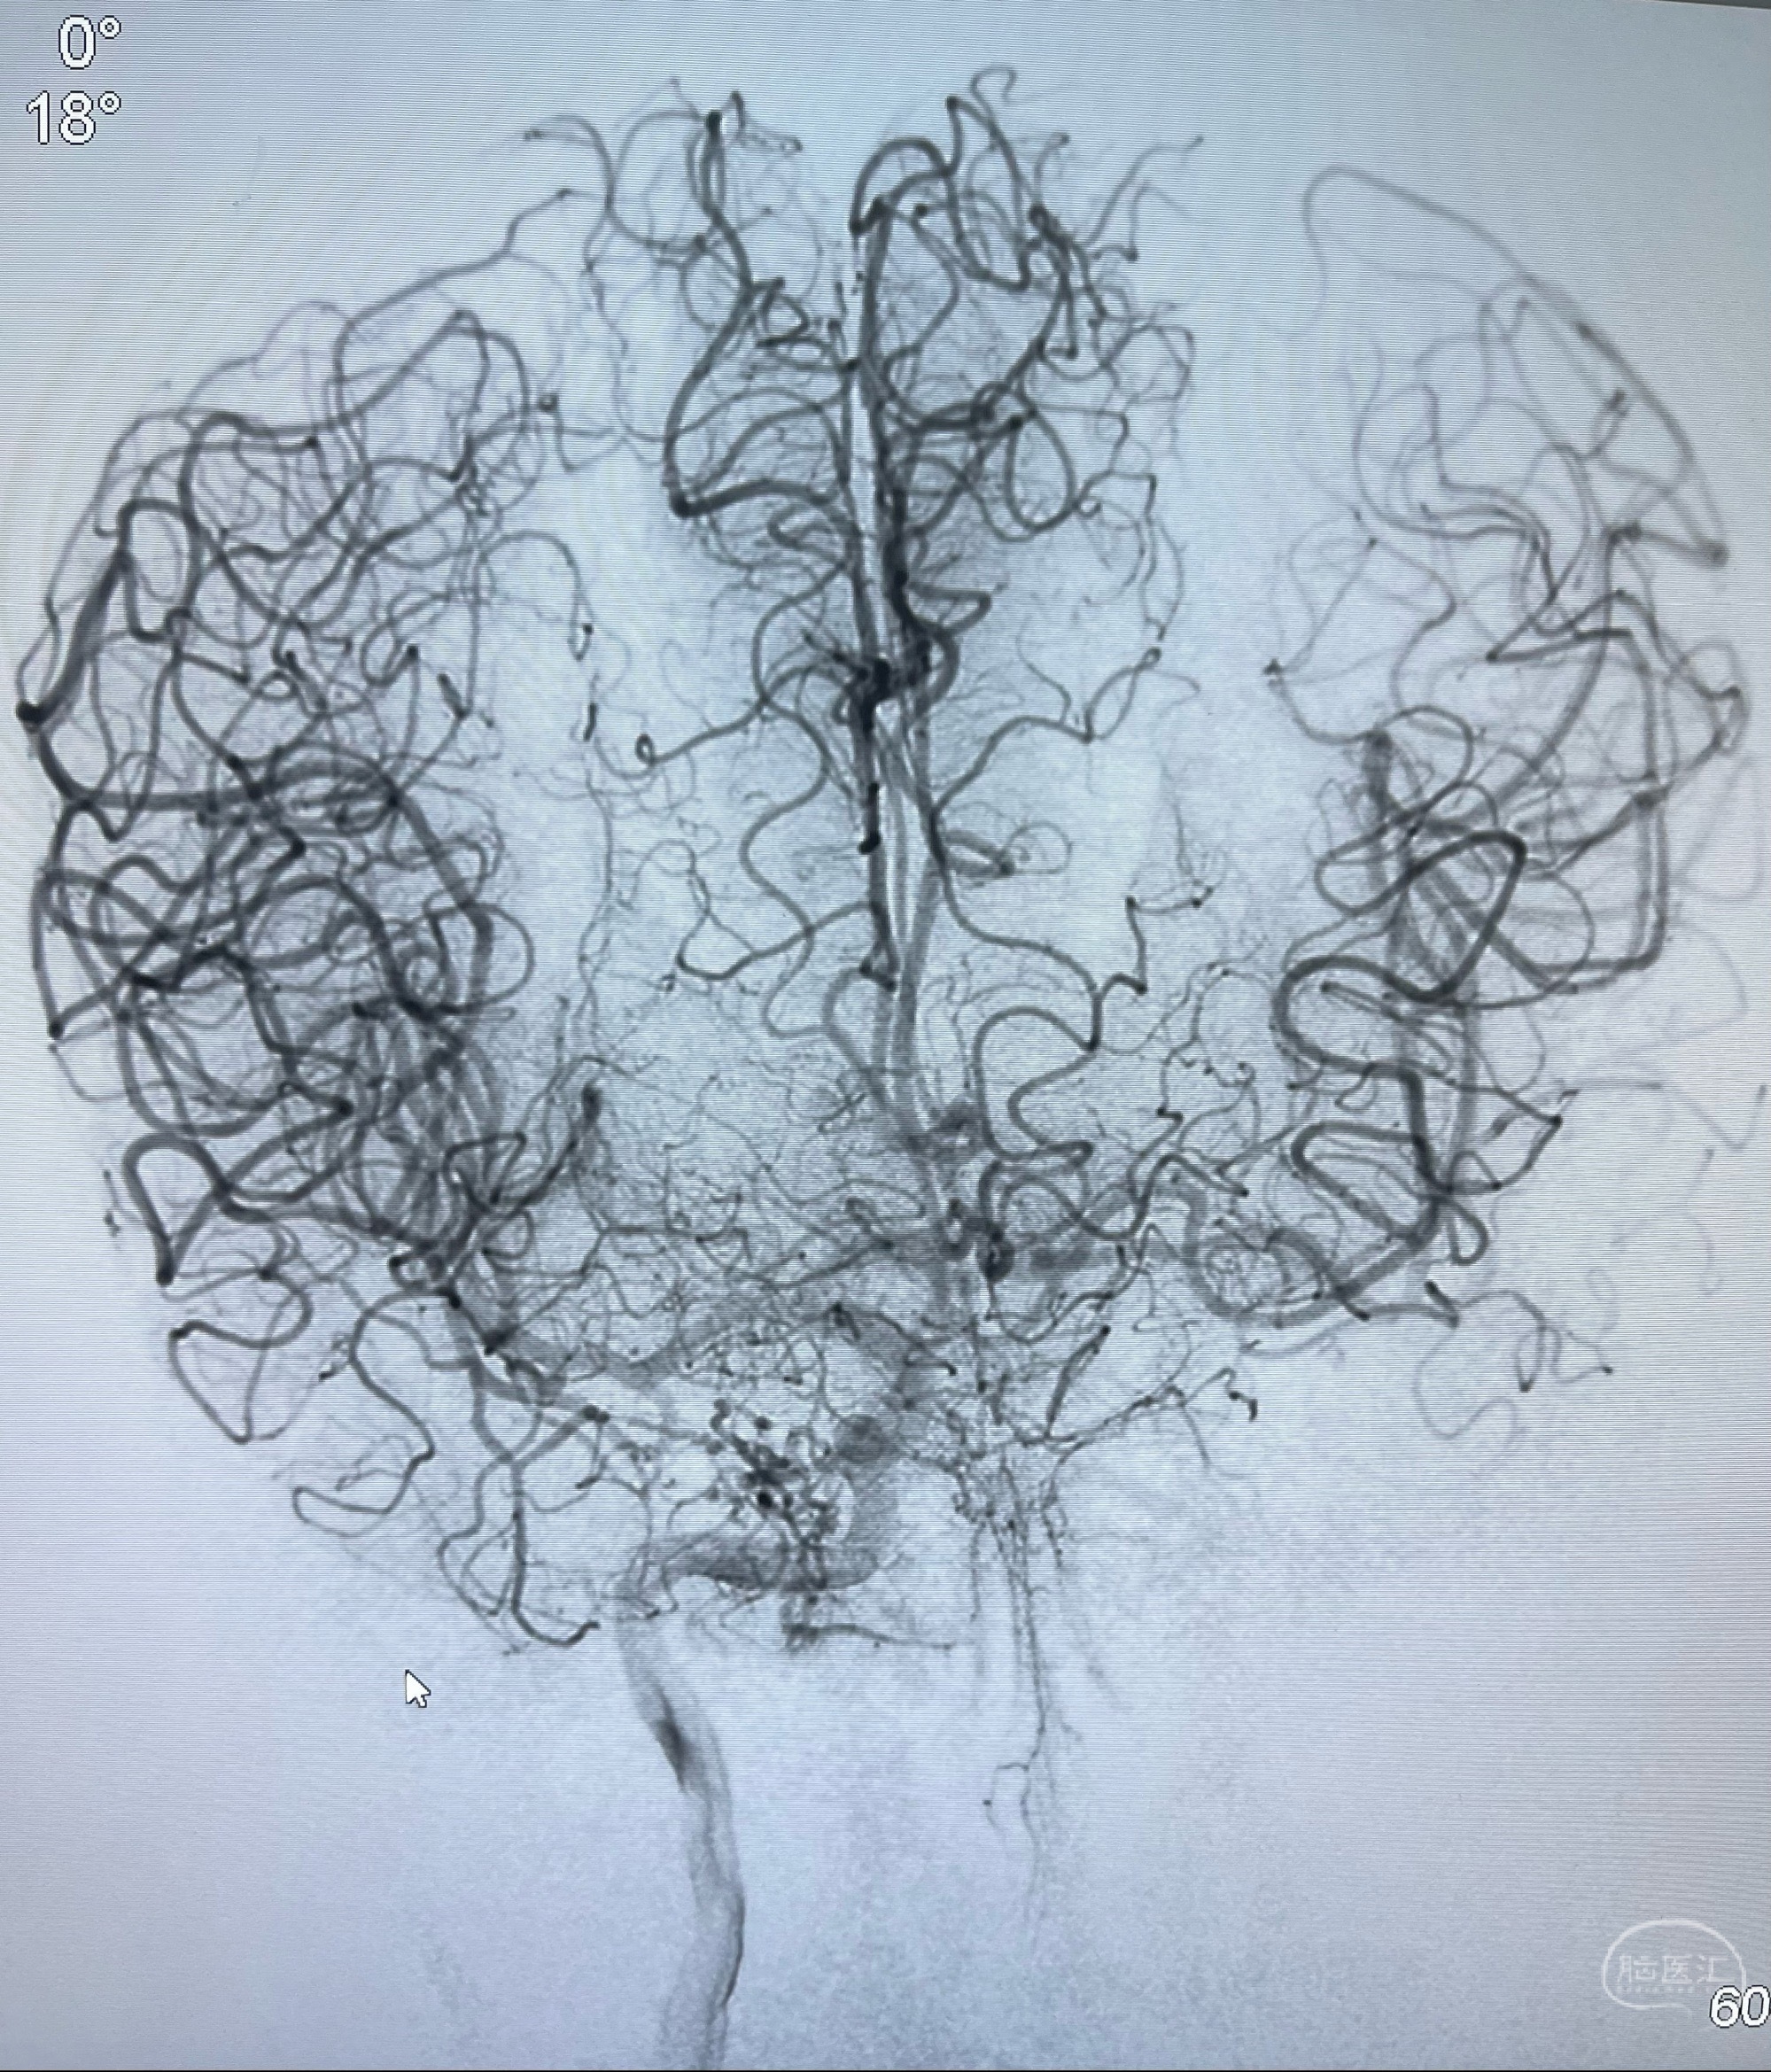

即刻造影显示狭窄扩张佳

即刻造影显示支架贴壁佳

支架完全打开,近心端位于原颈动脉支架远心端内

术后给予替罗非班300ug/h维持,序贯阿司匹林100mg➕泰嘉75mg口服